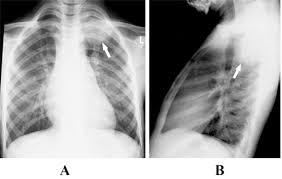

This growth can spread beyond the lung by the process of metastasis into nearby tissue or other parts of the body. Fluid which may accumulate between the lung and chest. Will lung cancer show on xray? Pneumonia is a common lung infection. Or, in people who smoke, they are thought to be related to tobacco use alone.

Lung Cancer Pictures Ct Scan X Ray And More from post.healthline.com The general prognosis of lung cancer is poor because doctors tend not to find the disease until it is at an advanced stage. When helen began coughing up phlegm in january she thought she just had a chest infection. Lung pathology of fatal severe acute respiratory syndrome. Lung cancer forms in the tissues of the lungs, most often in the cells that line air passages. Lung tumors can block the airway, causing frequent infections such as chest pain: An infection or abscess is perhaps the most common cause behind a mass that is mistaken for a tumor. An ache or pain when breathing or coughing. Although people who have persistent chest infections.